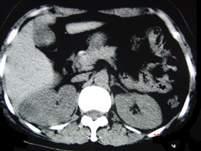

问题 女,12岁,右腰部疼痛10天,尿检可见大量的脓细胞CT平扫+增强如图所示,应诊断为 ( )

选项 A、右侧肾癌 B、右肾结核 C、右侧感染性肾囊肿 D、右肾转移瘤 E、右肾脓肿

答案 E